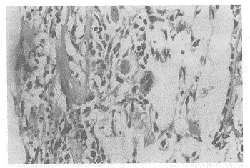

镜下可见培养前的骨干是一透明的软骨雏形,骨干区被一薄的骨膜骨领所包绕。培养48 h后,对照组成骨组织和间充组织所包绕的骨膜骨领均有所增加,骨干部位出现许多空腔隙 ,其间可见间充组织,并出现破骨细胞。10-7mol/L雌酚酮组骨外膜骨领的成骨组织 和骨小梁增多,骨髓腔形成并有骨小梁出现(图1,2)。

Fig.1 Photomicrograph of an ulna from mouse fetus cultured

for 48 h to show extensive periosteal bone collar and invasion

of mesenchymal tissue into the diaphysis(H.E×400)

Fig.2 Photomicrograph of an ulna from mouse fetus cultured

for 48 h at 10-7mol/L estrone to show bone trabecular and bone marrow(H.E×400)